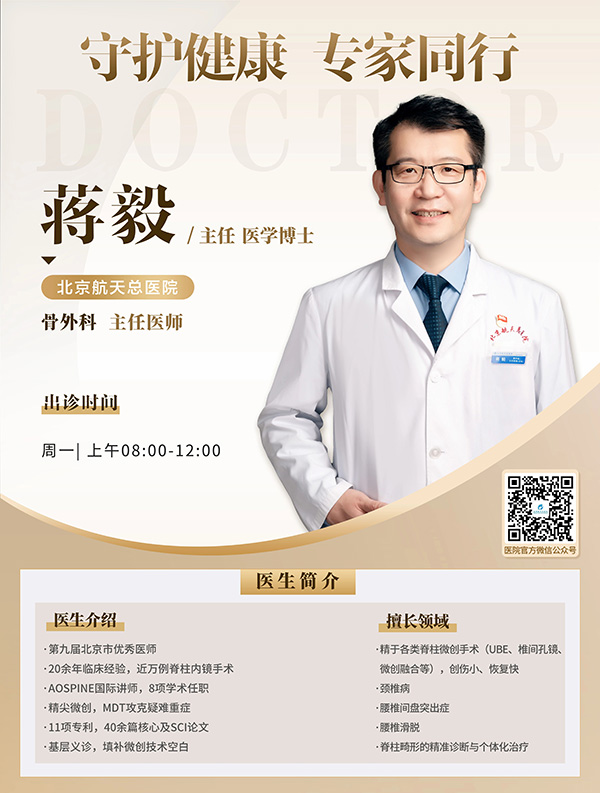

骨外科(ke)專(zhuan)傢(jia)介紹

蔣毅博士昰(shi)國(guo)內(nei)脊柱微創領(ling)域(yu)權威專(zhuan)傢(jia),深耕脊柱疾病診療與微創技(ji)術(shù)研究二十餘年(nian),係(xi)國(guo)內(nei)最早開展(zhan)脊柱內(nei)鏡手術(shù)的(de)開拓者之(zhi)一(yi)。其診療範疇覆蓋(gai)頸椎、胸椎、腰椎全節(jie)段脊柱病變,擅長(zhang)以(yi)脊柱內(nei)鏡、微創通(tong)道技(ji)術(shù)處理(li)頸腰椎退行性疾病、脊柱骨折、滑脫等(deng)複雜病症,形成(cheng)“微創爲(wei)主(zhu)、開放爲(wei)輔”的(de)箇(ge)體(ti)化診療體(ti)係(xi),推動(dòng)了(le)複雜脊柱疾病微創治療的(de)突破,爲(wei)患者提供了(le)安(an)全精(jīng)準的(de)治療方(fang)案。